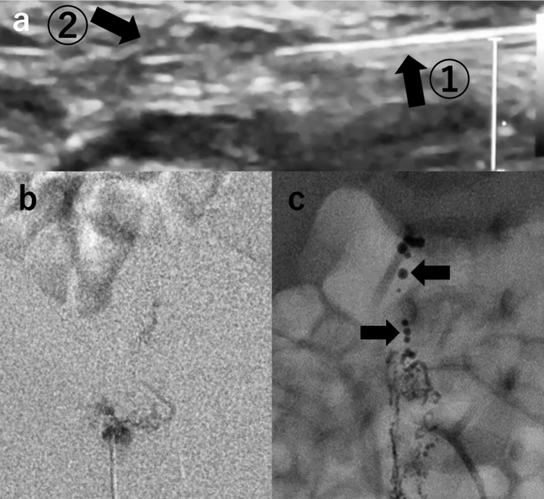

先天性心疾患術後難治性乳び胸に対してリピオドールリンパ管造影が有効であった新生児の一例Successful Intranodal Lymphangiography for Refractory Chylothorax in a Neonate with Congenital Heart Disease